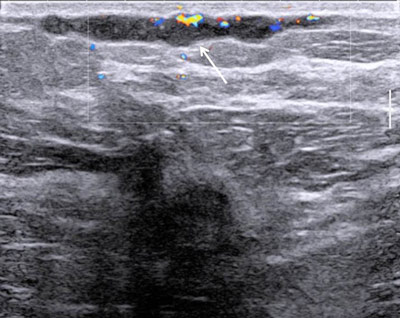

Figure 3

2D ultrasound with color Doppler: no vascularization inside the linear structure.